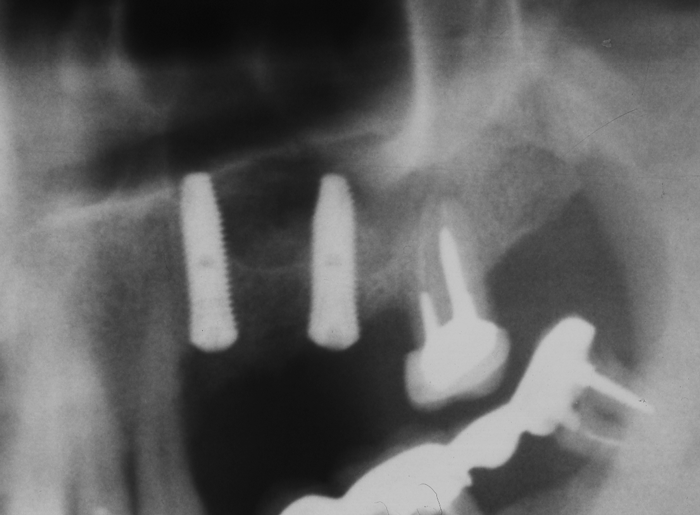

Схема на открития синуслифтинг

Видеоклип за открит синуслифтинг Пластинка Сasios